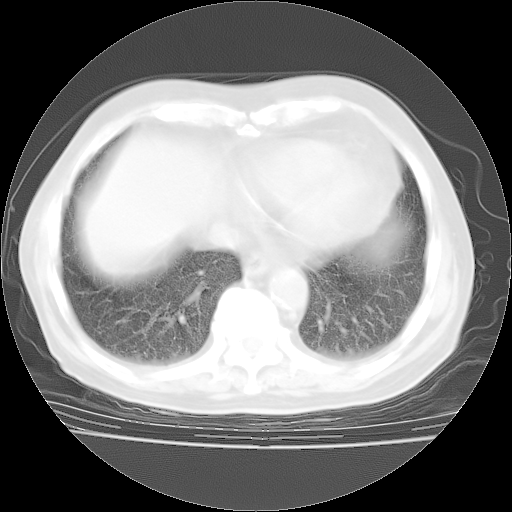

4月28日肺部CT——再次出现类似去年5月9日——磨玻璃样、间有“粟粒样”改变。

4月28日肺部CT——再次出现类似去年5月9日——透光度降低,“间质性”改变。

今请临免主任会诊后认为:4月14日胸部CT已有双下肺间质性改变。患者病情复发多系激素减量过快不正规所致。目前甲强龙80mg/日,一周后酌情开始减量,不易过快。环磷酰胺若已停用,暂不使用。他同意目前抗菌药物使用,但应考虑是否加用B-内酰胺类抗菌药物(中性细胞明显增高);2、结核复发目前依据不足;3、若免疫全套各项指标正常,考虑多系特发性肺间质炎可能大。4、加强支持,并注意保护胃黏膜。

今上午去请教了临免、呼吸主任:1、介绍病史和阅读系列胸部CT一致认为:患者肺结核不考虑,仍为肺间质纤维化,目前处于急性肺泡炎阶段。2、若仍发热,可将甲强龙增至:80mg Bid静滴,同时鉴于中性增高,合并细菌感染可能,继续左氧氟沙星治疗,再联用B-内酰胺抗菌药物,如头孢哌酮--舒巴坦;3、停用抗痨药;4、目前甲强龙每日剂量160mg ,体温正常后再酌情减量;目前暂不用免疫抑制剂;4、不建议使用免疫增强剂等;5、加强支持治疗,鼓励患者进食;5、注意随访肝、肾功及血常规情况;6、因患者目前激素用量较大,加用胃黏膜保护剂,防止消化道出血可能。